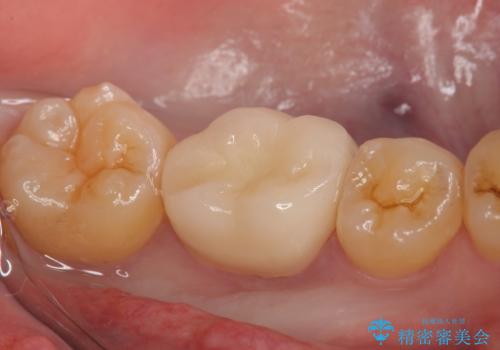

虫歯除去後、オールセラミッククラウンによる補綴を行いました。

今回用いたオールセラミッククラウンはジルコニアフレームという白い素材の上にセラミックを盛っているため、審美性が非常に高いのが特徴です。

また、ジルコニアは人工ダイヤモンドの材料にも使われているほど高い強度を持っており、そのためオールセラミッククラウンは審美性だけでなく、奥歯やブリッジの補綴も可能とするクラウンです。